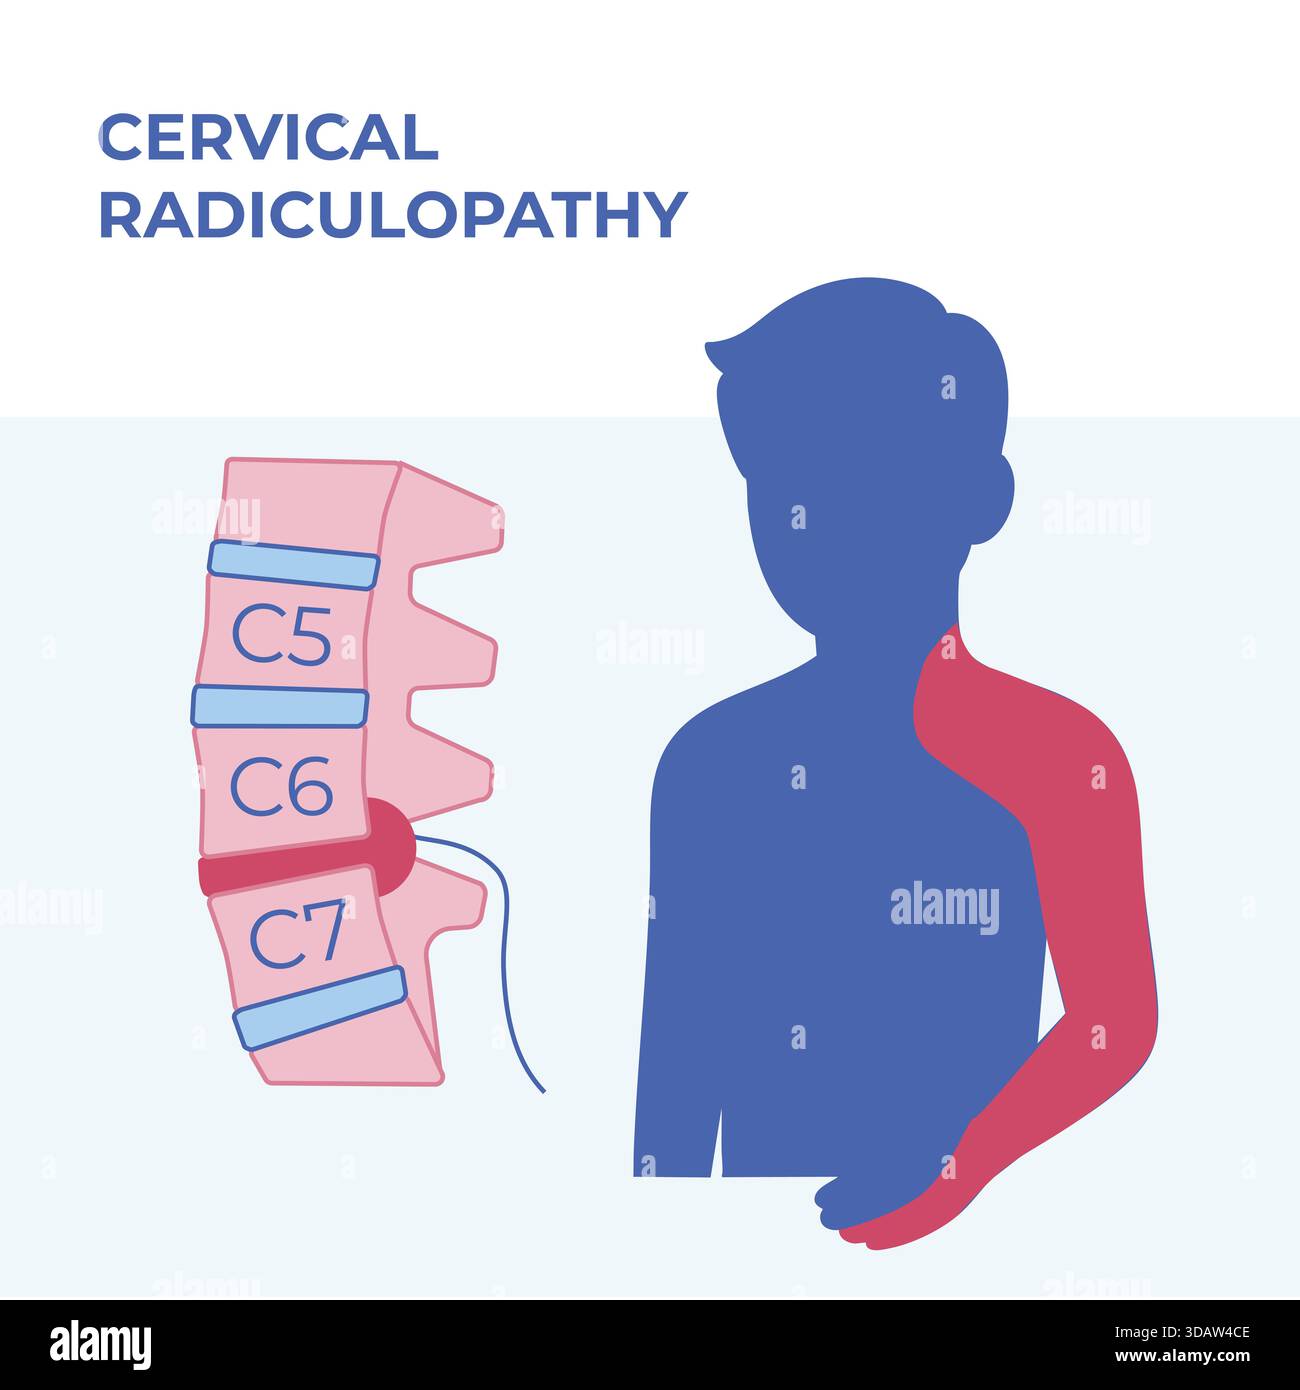

RF3DAW4CJ–Vektor-Illustration, die Schmerzverteilungsbereiche zeigt, die mit zervikaler Radikulopathie assoziiert sind, wobei Nacken-, Schulter- und Armregionen hervorgehoben werden. Vereinfacht

RF3DAW4CE–Vektormedizinische Illustration der zervikalen Radikulopathie mit Bandscheibenvorfall und entsprechenden Schmerzbereichen in Hals, Schulter und Oberschenkel.